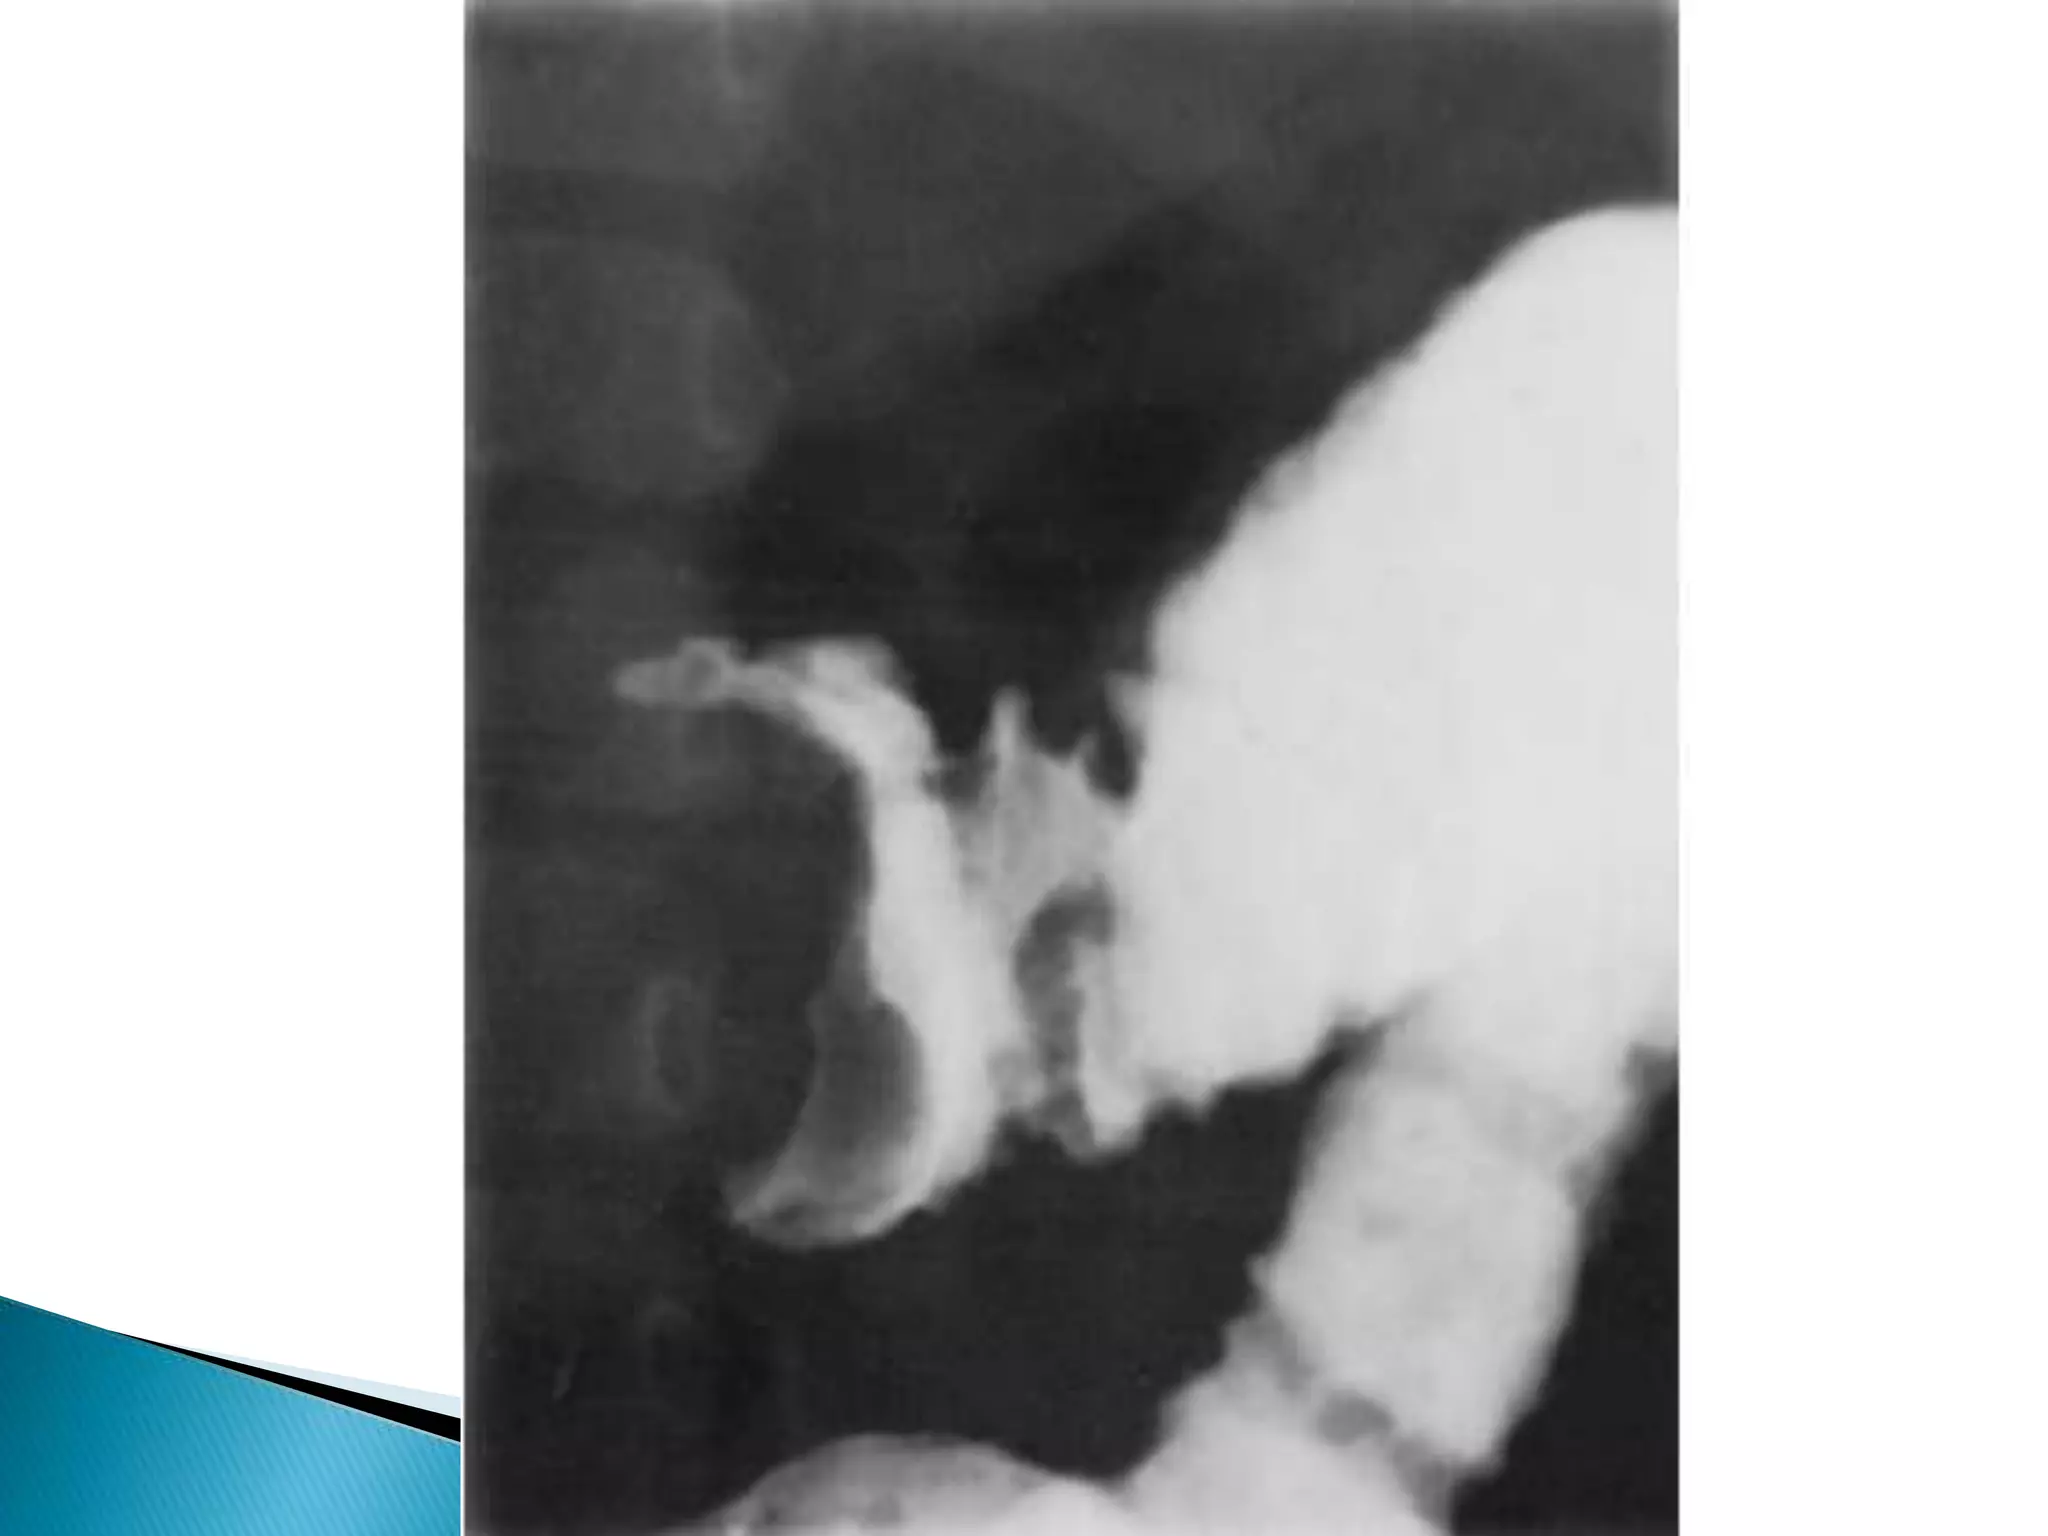

 the rounded barium column suddenly

becomes concave

 forms a meniscus around the head of the

intussusception

 When the intussusception is displaced, the

meniscus flattens out

 barium seeps between the two and produces

the characteristic radiologic appearance of a

coiled spring

 Filling of the cecum is often slow, the sudden

rush of barium into the distal ileum indicative

of reduction